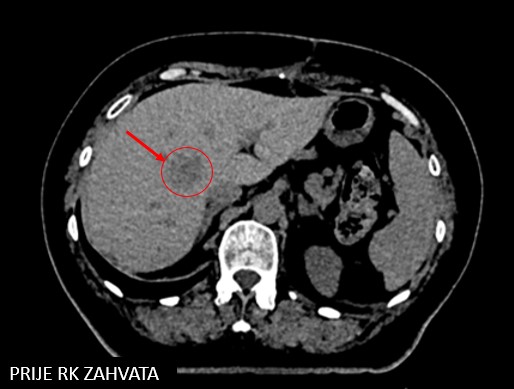

SABR meta seg. IVA hepatis (17.7.2018.)

Rezultat – 58 mjeseci nakon RK

Potpuni nestanak tretirane lezije